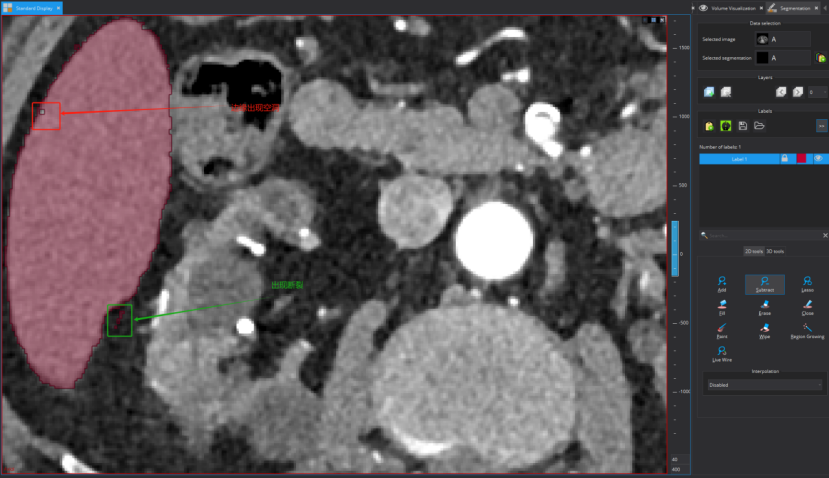

点击之后可以进行标注了,这个地方可选择的标注工具比较多,下图框出部分即为标注相关工具,标注者需要进行摸索尝试一下!需要用什么标注工具,选择一下即可,然后在图上进行标注及修改

标注示例

下面我进行标注一层进行展示,以更快学习使用,还是分步骤实现吧!(以标注肝脏为例子)

Step 1:点击标注工具add

Step 2:沿着标注目标边缘勾勒

以看到我的勾勒超出肝脏区域了,此外标注的颜色太浓会影响我对标注边界的判断。所以需要对标注进行:1)淡化标注颜色;2)修改标注。

针对问题1,调节标注颜色透明度:

针对问题2:点击下图按钮,然后沿着超出边界部分边缘进行勾画即可消除超出区域(注意:如果是标注不足,则是点击add,对不足区域的边缘进行勾画即可补上不足区域)

修改后的标注如下图所示:

尽管上图标注看似不错,但仍可以进一步精细修改。鼠标指向标注目标区域,按住鼠标右键进行放大

精修后的可视化如图: